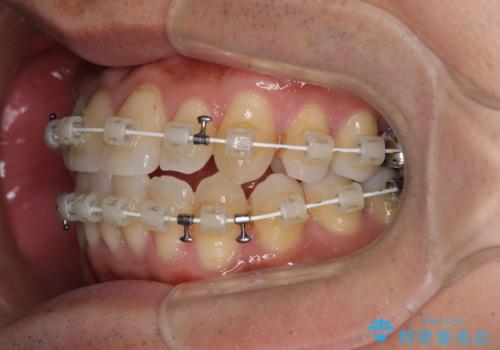

- 審美装置

- 1年2ヶ月

前歯のクロスバイトは、改善の途中で歯髄壊死を起こすリスクが高くなるため、マウスピース矯正よりもワイヤー矯正をお勧めしております。

この患者様もクロスバイトはあっという間に改善され、1年強で速やかに治療を終えることができました。